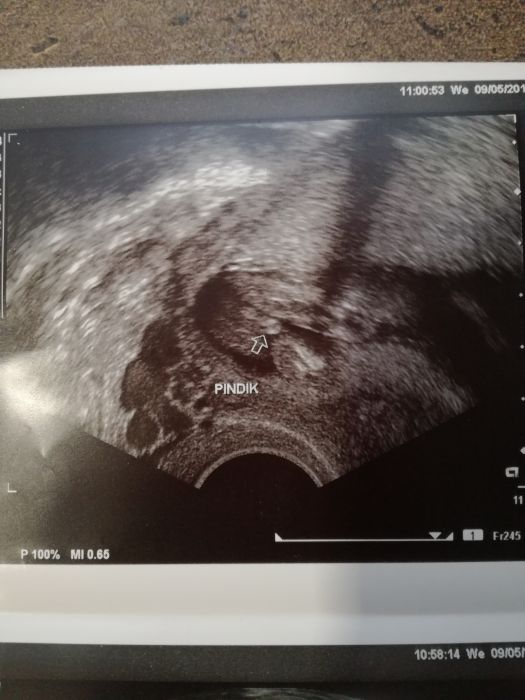

Ahoj holky, tak se hlásíme z kontroly. Prcek ok, vše v pořádku. Screening i krev taky, jen jsem dostala železo, ale to jsem měla i u první. Kolik měříme nevím, bude se měřit na velkém utz ve 20tt, kam se máme objednat. Jinak čekám kluka :) asi teda.. Dr. říkal, že mimčo je ještě malé, ale pindíka jsme viděli oba :D příště ještě potvrdíme. Hodím Vám sem fotky.

Můj chlapák :* :)